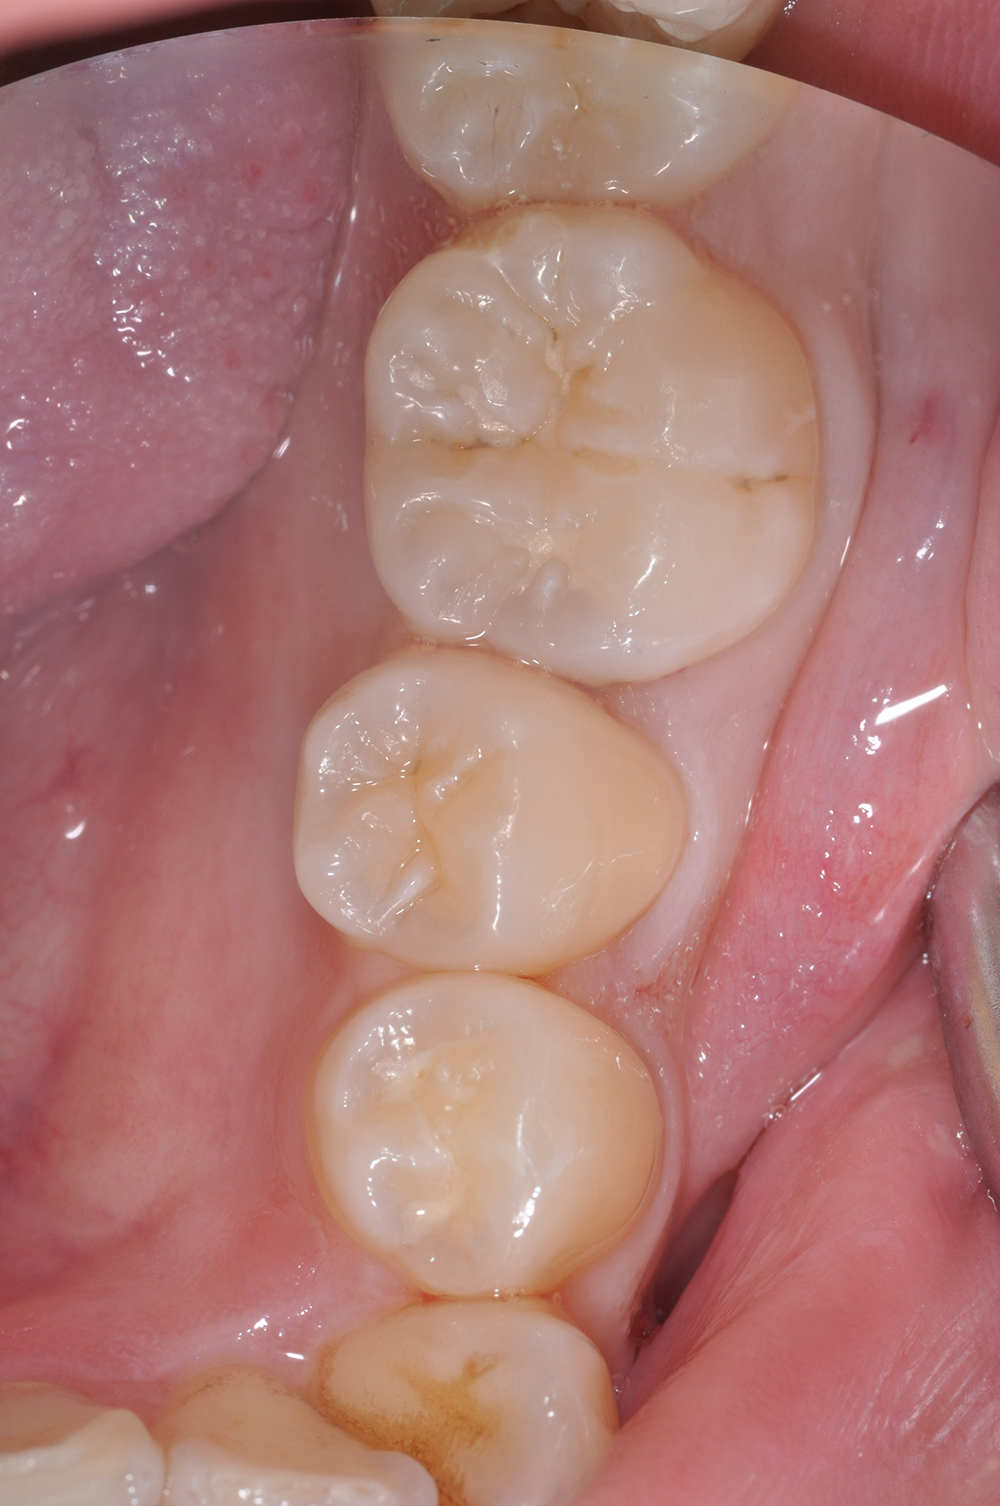

術前

術後

世代・性別

60代男性

主訴

歯ブラシで出血するので見てほしい

治療内容

ブラッシング指導、歯周基本治療、虫歯治療、根管治療、補綴治療

治療期間

6ヶ月

治療費

保険適応内

治療のリスク

治療後にしみる・痛みが出ることがある